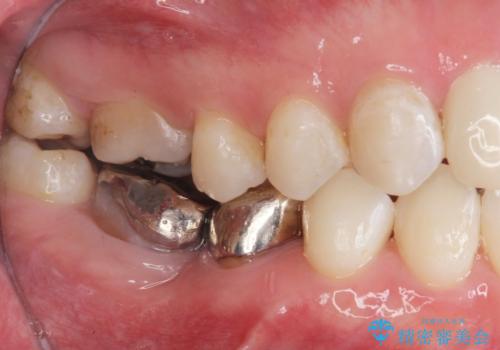

銀歯を白くしたい セラミック治療

- 見栄えが悪く、歯ブラシのしづらい銀歯を白くしたい、とセラミック治療を希望され来院されました。

歯が傾いているため、歯間ブラシや歯ブラシのしやすさを考慮し、汚れの溜まりにくいようなクラウン設計を行います。

- 26.4万円(ジルコニアクラウン×2・仮歯×2)費用は治療当時の料金となります